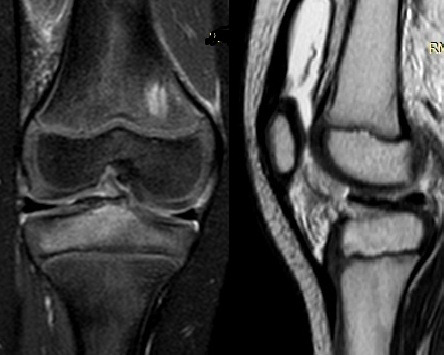

Plain anteroposterior and lateral radiographs demonstrated a bony fragment detached from the tibial plateau at the level of the tibial spine, consistent with a partially displaced, but not rotated, ACL avulsion fracture (Figure 1). The fracture was classified as a Type II Meyers and McKeever lesion based on radiographic features. Magnetic resonance imaging (MRI) confirmed the diagnosis, showing avulsion of the tibial spine with a fragment arising from the tibial eminence, associated bone marrow edema, and soft-tissue swelling. No meniscal tear or intermeniscal ligament entrapment, chondral lesion, collateral ligament injury, was detected (Figure 2).